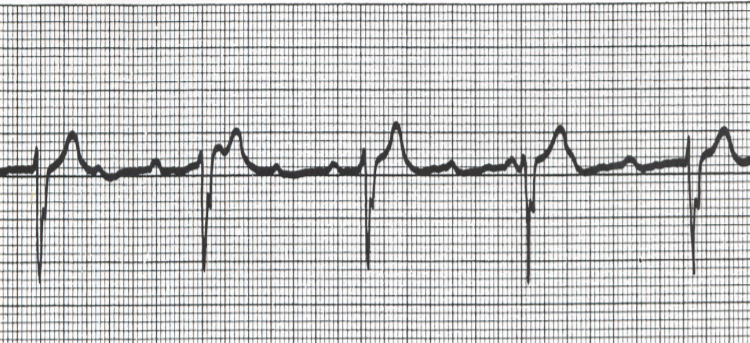

What is depicted in the EKG

Complete (third Degree) heart block

Right Bundle Branch Block